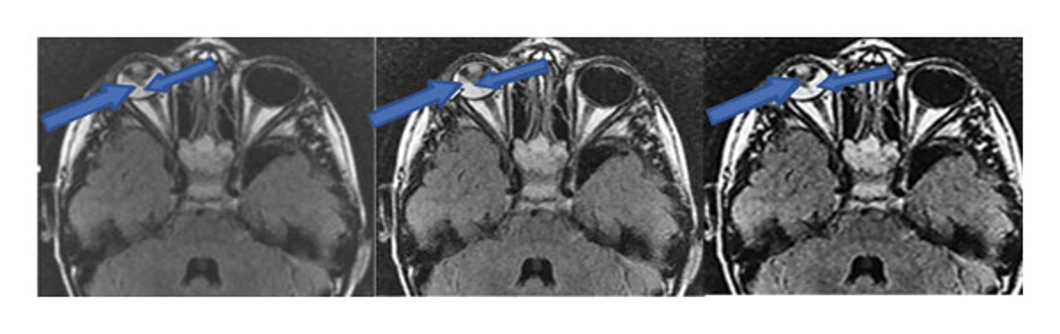

Traditional MRI CNN 3D CNN

One condition of long term diabetes is Diabetic Macular Edema (DME) which can severely impact your vision.

MRI images of the eyes are used to detect this condition and the presence of lesions.

AI, such as CNN and 3D-CNN, can significantly increase the details and clarity of the images, making diagnosing DME more effective.

Example Benefit of AI: Deep Learning for Imaging Diagnostics

One study proved that applying these techniques approved diagnostic accuracy.

- 3D-CNN also performed bettter with critical diagnostic metrics like Dice value, sensitivity, and specivifity, as well.